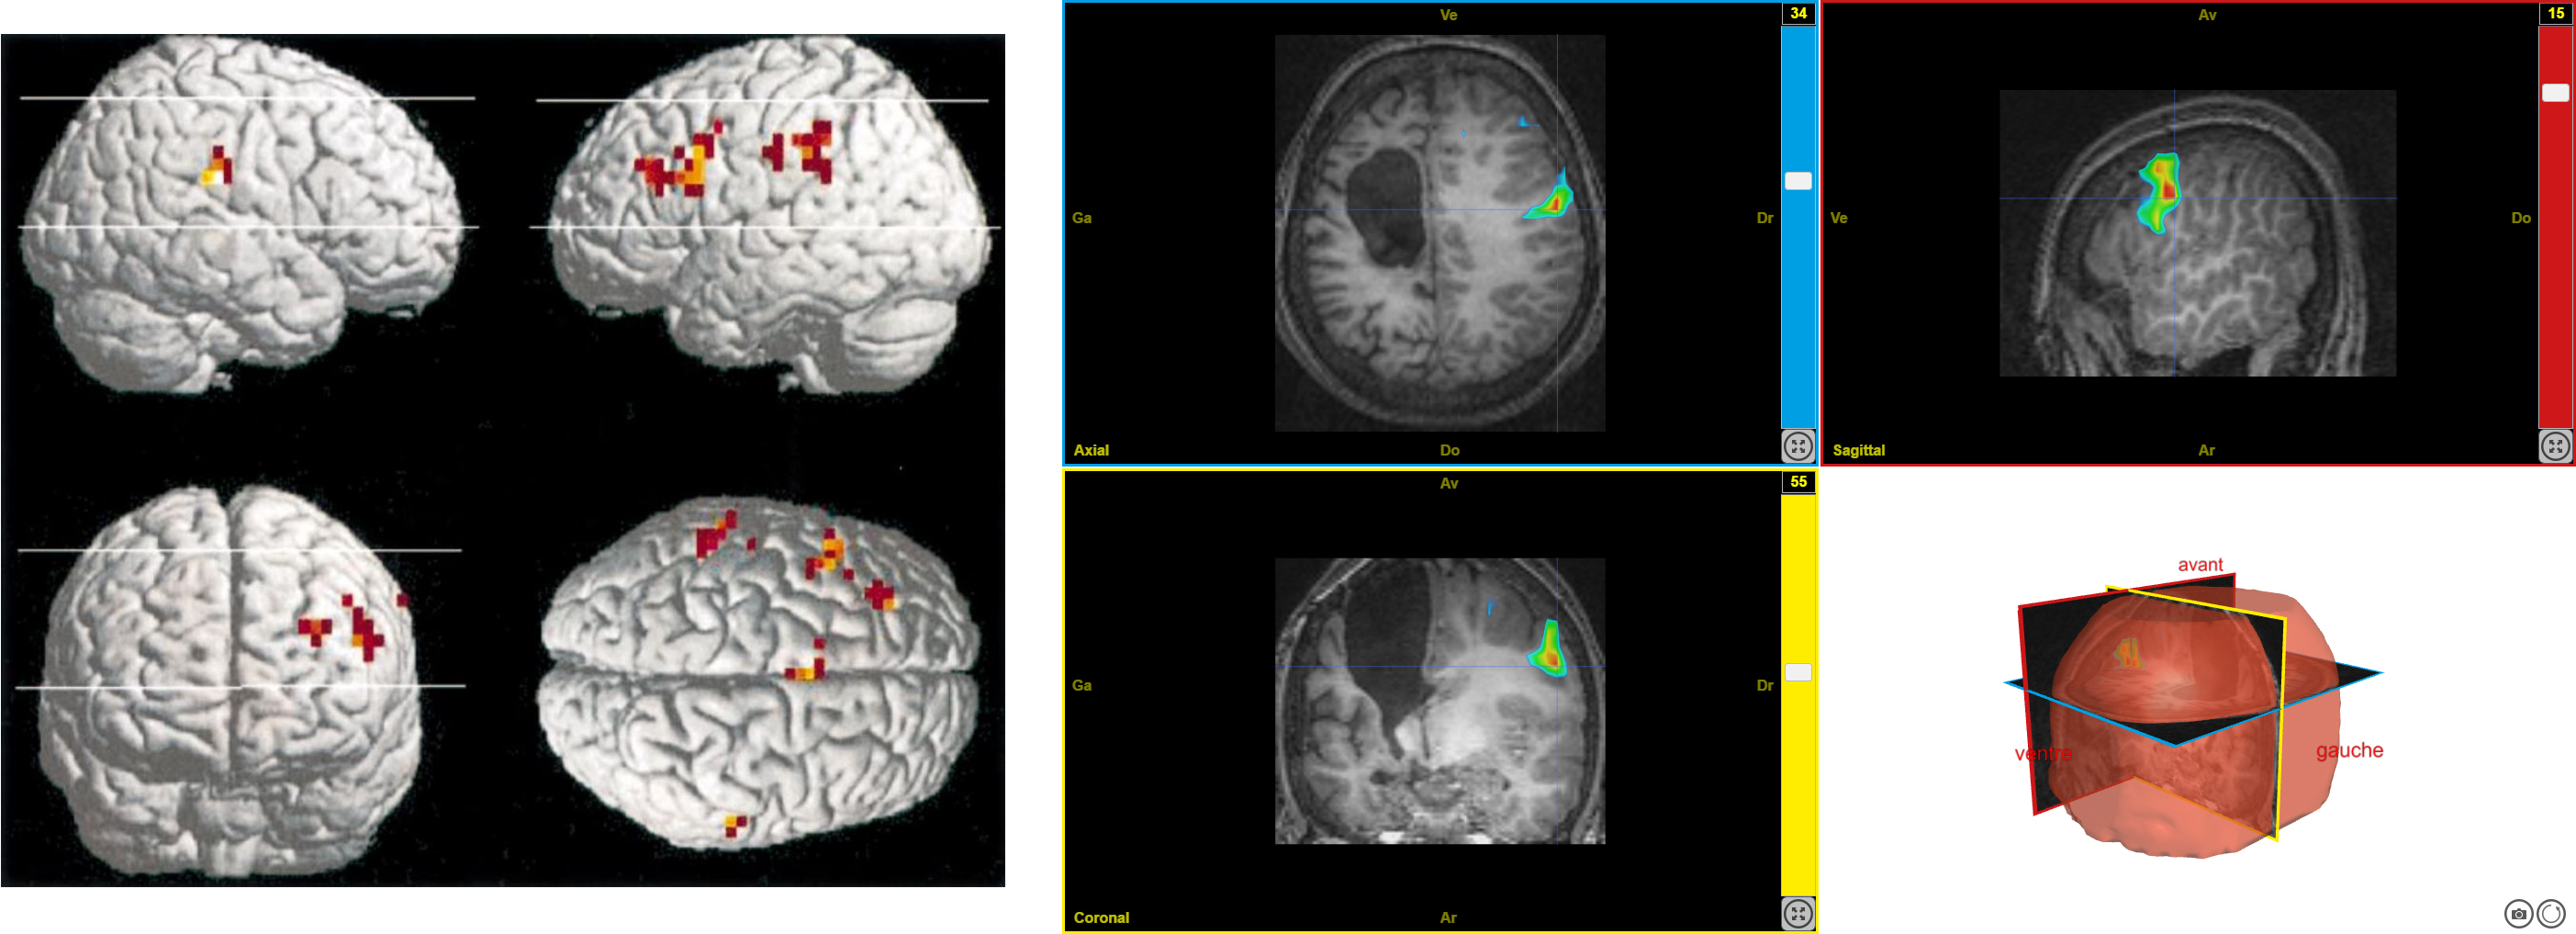

plasti7

Image dans sa taille originale :

703 ko

Ancien logiciel : EduAnatomist et Neuropeda

Informations sur les images AnaPeda

Exemple de lien direct vers EduAnat 2 en ligne